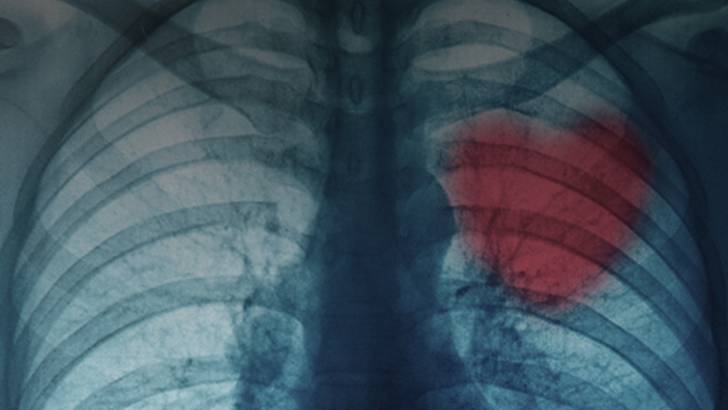

Although most bypass grafts are sourced from other parts of a patient's body, bioengineers are examining new materials that might be used for bypass grafts to reduce the risk of second-site complications. Silk has been a standard material in sutures for decades, and is now showing promise as a biomaterial in bypass grafts. Might silkworms help repair clogged arteries? Dr. David Kaplan, endowed chair, the Stern Family Professor of Engineering, and professor & chair of the department of biomedical engineering at Tufts University, discusses the advantages of silk protein as a biomaterial and related applications to cardiology. When might this new technology be applied from the bench to the bedside? Dr. Janet Wright hosts.